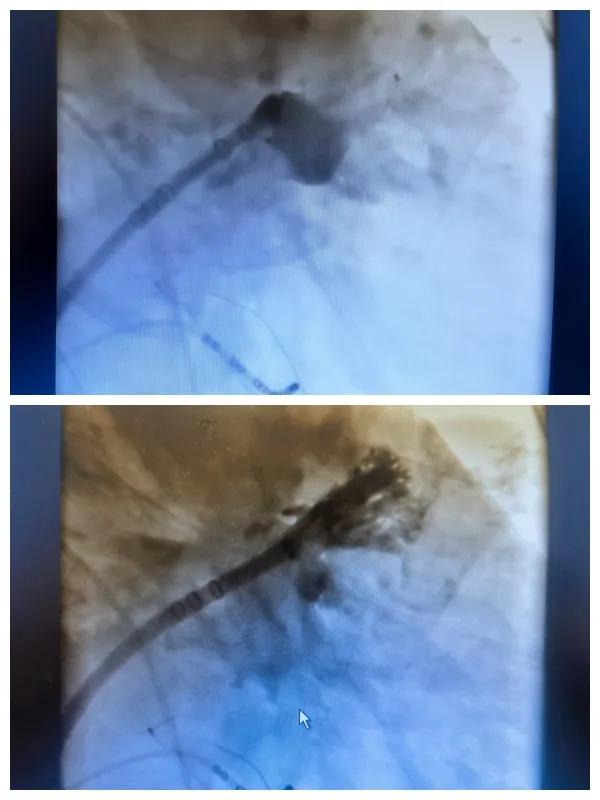

漯河市二院成功開展房顫射頻消融術(shù)+左心耳封堵WM FLX一站式手術(shù),再攀“心”高峰!

房顫射頻消融術(shù)+左心耳封堵WM FLX一站式手術(shù)

6月26日,市二院成功為一名老年房顫患者實(shí)施了房顫射頻消融術(shù)+左心耳封堵WM FLX一站式介入治療,標(biāo)志著醫(yī)院在心律失常介入治療領(lǐng)域邁出了嶄新的一步,開啟了新的治療篇章。

本次手術(shù)特邀我國(guó)著名心血管內(nèi)科專家、河南省胸科醫(yī)院黨委書記袁義強(qiáng)及血管內(nèi)科七病區(qū)主任黃瓊教授蒞臨指導(dǎo),市二院院長(zhǎng)王瑾帶領(lǐng)心血管內(nèi)科電生理等專家團(tuán)隊(duì)緊密合作,一次性解決了患者房顫、血栓兩大困擾,也使患者告別了終身服用抗凝藥的痛苦,極大地降低了患者的經(jīng)濟(jì)和用藥負(fù)擔(dān)。

為了讓患者得到全面、綜合的治療,經(jīng)過團(tuán)隊(duì)術(shù)前充分討論,并征得家屬同意,心血管內(nèi)科團(tuán)隊(duì)決定采用目前國(guó)內(nèi)外先進(jìn)的房顫射頻消融術(shù)+左心耳封堵WM FLX一站式介入微創(chuàng)手術(shù)來治療老人的疾病。整個(gè)手術(shù)過程圓滿順利,術(shù)后何大爺各項(xiàng)體征正常,蘇醒后順利返回病房。